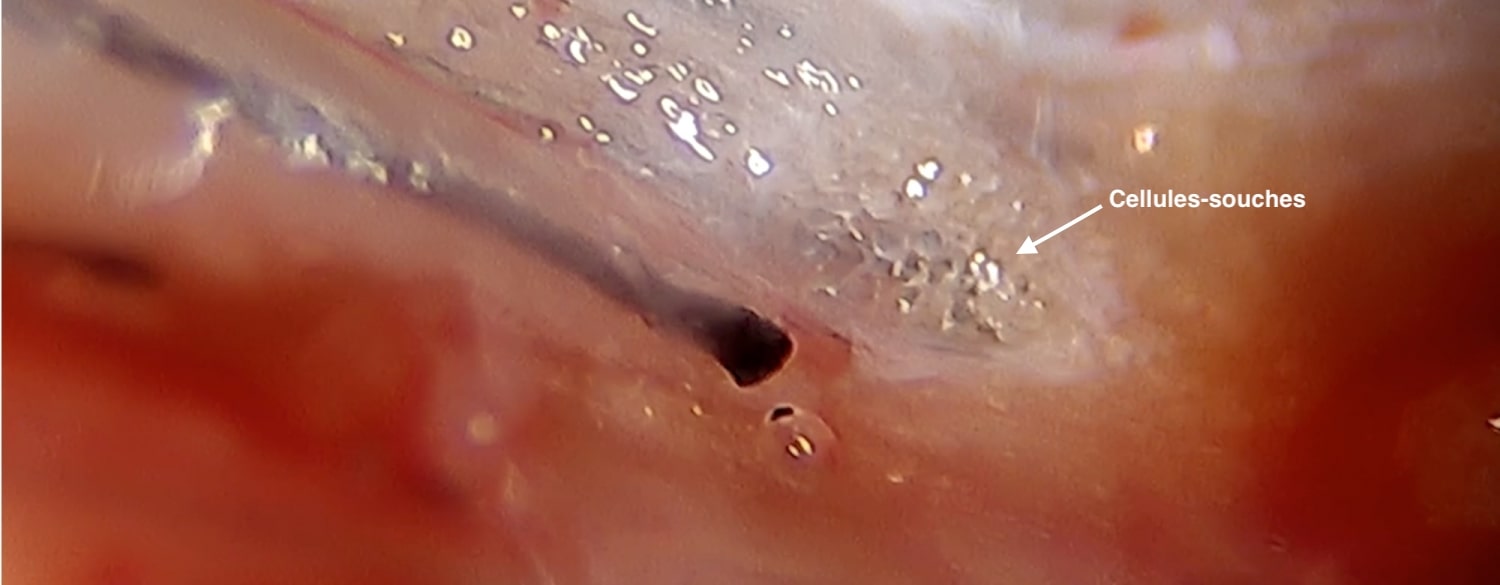

In our NHT Europe clinic, we use this advanced procedure, derived from this fat autograft technique: We successively filter the fat sample (nano fat graft) more and more finely, which allows us to obtain higher concentrations of stem cells (mesenchymal stem cells); the analyses of these samples show a total destruction of the adipocytes, but they contain the stromal vascular fraction (SVF) with a concentration of stem cells identical to those obtained by enzymatic digestion of the fat. These will improve tissue trophicity, soften scars and allow hair transplantation to be carried out under better conditions.

The procedure consists of taking a few cubic centimetres of fat under local anaesthesia, centrifuging it, and filtering it with increasingly fine filters to get a solution containing a high concentration of so-called multipotent stem cells, which are able to recreate many tissues.

This is a procedure that allows the harvesting and activation of autologous hair follicle stem cells (HFSC) thanks to a few pre-collected grafts; a mechanical disaggregation is then carried out by rotary filtration of the grafts and the filtrate reinjected by mesotherapy: hair mesograft.